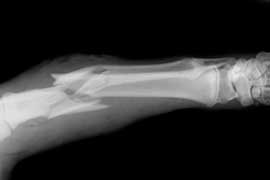

Guía actualizada para el tratamiento de la osteoporosis

El American College of Physicians recomienda el tratamiento farmacológico de la osteoporosis durante cinco años, y desaconseja el monitoreo de la densidad mineral ósea durante ese lapso. Annals of Internal Medicine, 9 de mayo de 2017